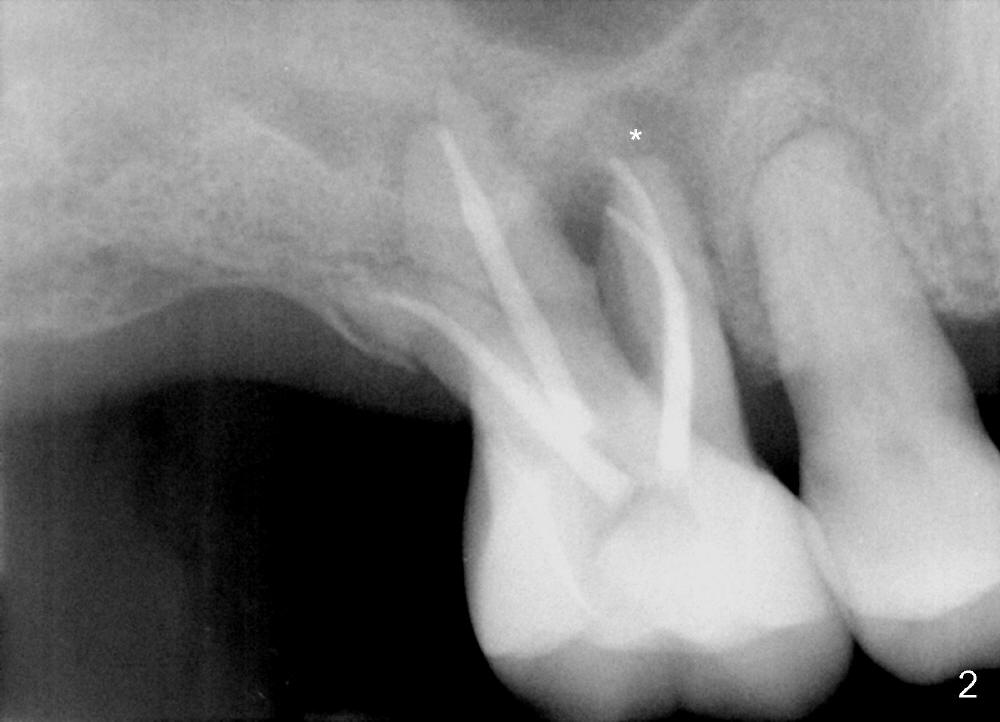

A 60-year-old man has poor dentition (Fig.1). The tooth #3 is symptomatic with a mesiobuccal fistula. PA shows large periapical radiolucency associated with the mesiobuccal root (Fig.2 *). It appears that the tooth is non-salvageable. The roots of this tooth are widely furcated. The septum should be large unless destroyed by infection.